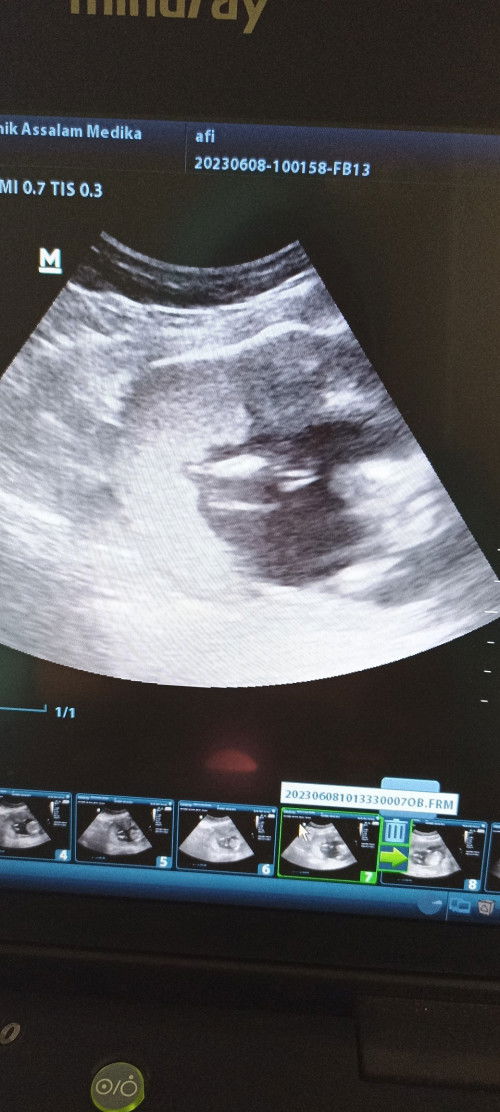

32 tahun hamil ke 2 cewek lagi

Curhat dong bun... Di usiaku yang ke 32 ini hamil 15 minggu, kayaknya cewek lagi deh. Walaupun bilang yang penting sehat, tapi aku yakin sebenernya suami juga pengen anak cowok. Jadi galau nanti harus promil lagi apa nggak ya? Aku juga pengen anak cowok, tapi kalau nanti 4-5 tahun dari sekarang promil lagi, aku udah masuk resiko tinggi dari segi usia. #perkiraan #jeniskelaminbayi